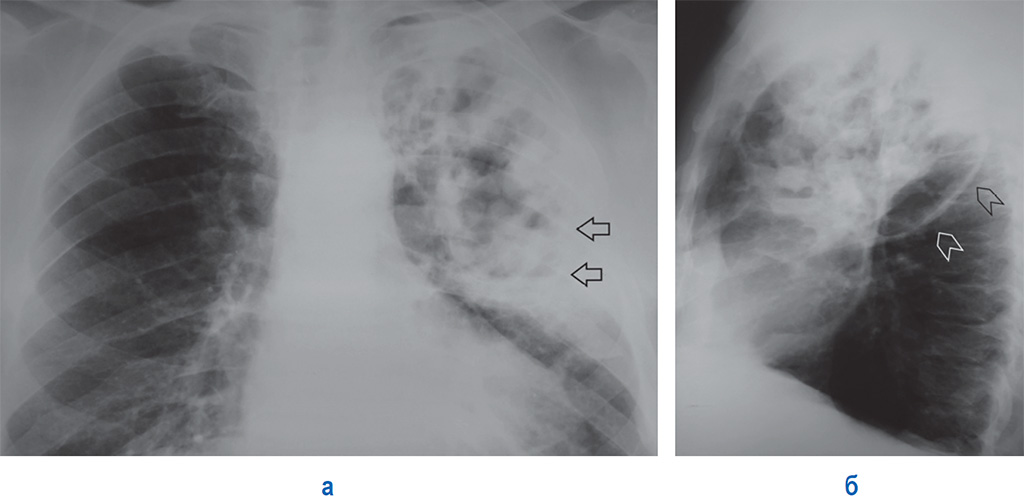

Бактериальная деструкция легких у детей презентация - 88 фото